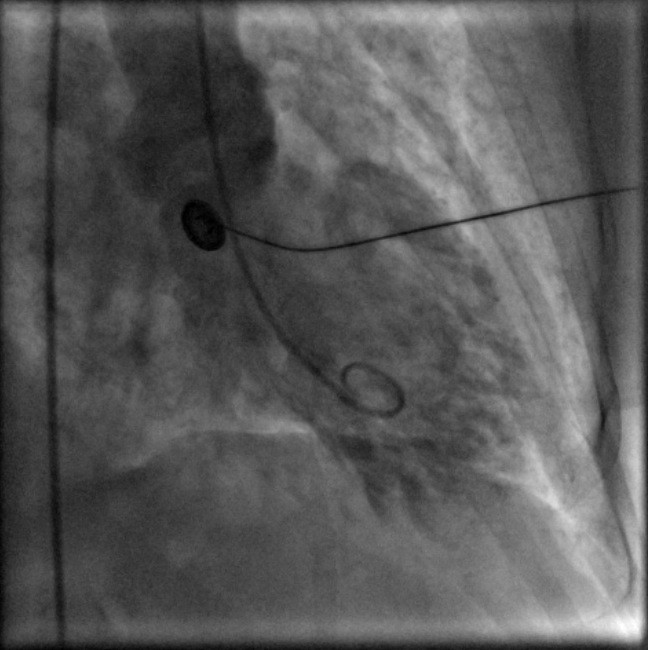

Left ventriculogram showing apical dyskinesis (ballooning) in systole Apical Ballooning Syndrome the most common abnormality in takotsubo cardiomyopathy — the one that gives the disorder its name —. takotsubo syndrome, also known as broken heart syndrome, is a condition where your heart muscle changes shape and suddenly. takotsubo syndrome (tts), also commonly known as takotsubo cardiomyopathy or apical ballooning. takotsubo cardiomyopathy—also called stress cardiomyopathy, apical ballooning. . Apical Ballooning Syndrome.